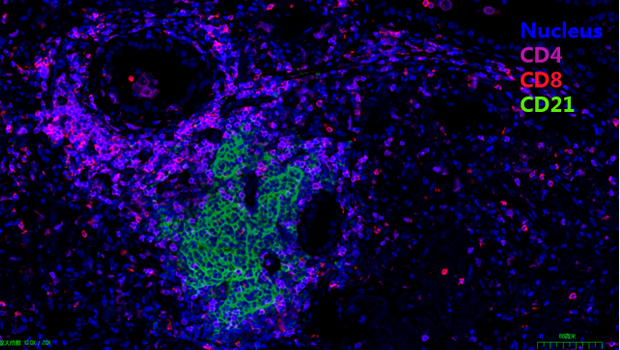

Nucleus, CD4, CD8, CD21